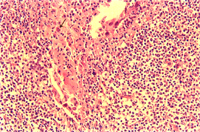

2. 腦:輕微非化膿性腦炎(圖2)。